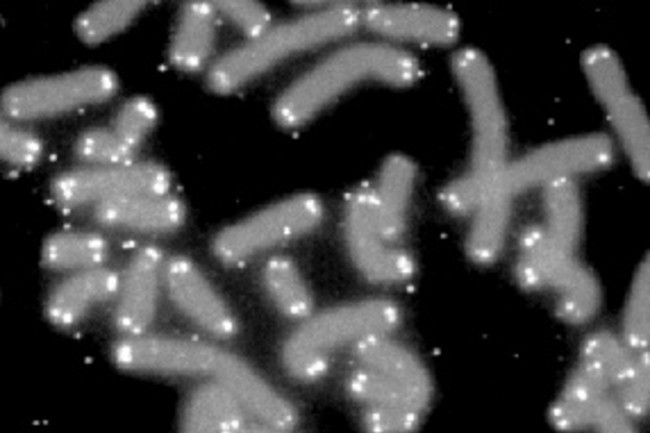

Khắp thế giới, rất nhiều công ty đang nghiên cứu những công nghệ để kéo dài tuổi thọ, thậm chí hồi sinh người chết.